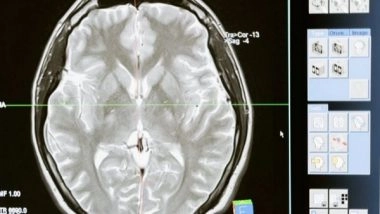

Washington [US], December 1 (ANI): Neuroscientists discovered that the adult brain contains millions of 'silent synapses' immature connections between neurons that remain inactive until they're recruited to help form new memories.

Until now, it was believed that silent synapses were present only during early development when they help the brain learn the new information that it's exposed to early in life. However, a new MIT study revealed that in adult mice, about 30 per cent of all synapses in the brain's cortex are silent.

The existence of these silent synapses may help explain how the adult brain can continually form new memories and learn new things without modifying existing conventional synapses, the researchers say.

"These silent synapses are looking for new connections, and connections between the relevant neurons are strengthened when important new information is presented. This lets the brain create new memories without overwriting the important memories stored in mature synapses, which are harder to change," says Dimitra Vardalaki, an MIT graduate student and the lead author of the new study.